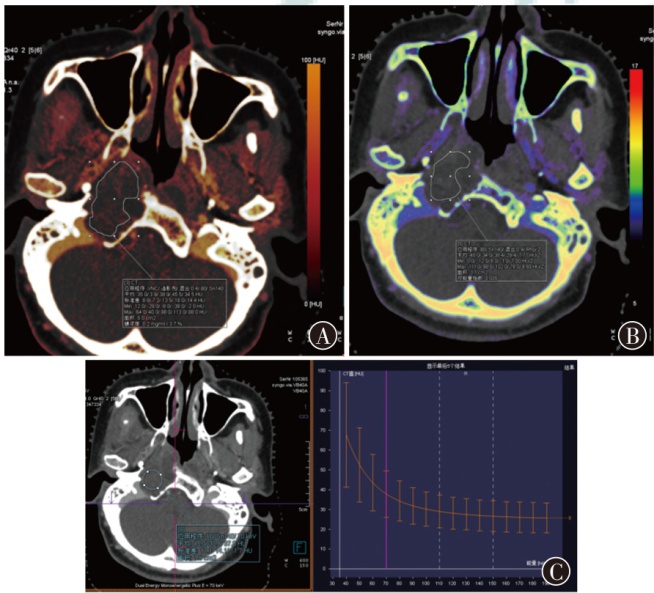

目的初步探索脊索瘤患者质子放疗前能谱CT定量参数与放疗前后MRI表观扩散系数(ADC)变化的相关性。方法回顾性分析2022年8月至2024年12月于山东省肿瘤防治研究院(山东省肿瘤医院)行质子放疗的28例脊索瘤患者的影像数据。收集治疗前能谱CT图像中病灶区域的相对碘浓度(RIC)、电子密度(ED)、有效原子序数(Zeff)及能谱曲线斜率(λHU)4个参数。同时收集放疗前后的MRI-DWI图像中ADC差值,记为ΔADC。通过散点图、一元线性回归、LOWESS曲线、相关性矩阵及Bootstrap等方法评估能谱CT参数与ΔADC之间的相关性。结果28例患者治疗前ADC为1 137.05(921.07,1 643.91),治疗后ADC为1 197.10(994.75,1 785.57),ΔADC为133.18(-36.46,253.04);RIC为0.45(0.12,0.67),ED为38.01±12.72,Zeff为8.40±0.64,λHU为-2.20±1.05。散点图结果显示,RIC与ΔADC之间的点状分布呈现正向趋势;λHU与ΔADC之间的点状分布呈现负向趋势。一元线性回归结果显示,RIC与ΔADC的拟合优度最高(R²=0.75),回归系数最大(β=518.34);其次为λHU(R²=0.64,β=-121.94);Zeff与ΔADC的拟合优度较低(R²=0.25);ED与ΔADC未发现相关关系。LOWESS曲线拟合结果与一元线性回归模型一致,未发现明显偏离趋势。相关性矩阵显示,RIC与ΔADC呈正相关(r=0.88,P<0.001),Zeff与ΔADC呈中等正相关(r=0.51,P=0.006),λHU与ΔADC呈负相关(r=-0.84,P<0.001)。Bootstrap重抽样分析结果显示,RIC、Zeff、λHU与ΔADC的r值分别为0.87、0.50、-0.80。结论脊索瘤患者质子放疗前能谱CT参数RIC与ΔADC呈正相关,λHU与ΔADC呈负相关。

ObjectiveTo preliminarily explore the correlation between the quantitative parameters of spectral CT before proton radiotherapy and the changes in apparent diffusion coefficient (ADC) of MRI before and after radiotherapy in chordoma patients.MethodsA retrospective analysis was conducted on imaging data from 28 patients with chordoma who underwent proton radiotherapy at Shandong Cancer Hospital and Institute from August 2022 to December 2024. Spectral CT images obtained prior to treatment were used to extract four quantitative parameters of the lesion area: relative iodine concentration (RIC),electron density (ED),effective atomic number (Zeff),and the slope of spectral attenuation curve (λHU). In parallel,MRI-DWI scans before and after treatment were collected to compute the ADC difference (ΔADC). The correlation between spectral CT parameters and ΔADC was assessed using scatter plots,simple linear regression,LOWESS curve fitting,correlation matrix,and bootstrap resampling methods.ResultsThe ADC of 28 patients was 1 137.05 (921.07,1 643.91) before treatment,and 1 197.10 (994.75,1 785.57) after treatment,and the ΔADC was 133.18 (-36.46,253.04). The RIC was 0.45 (0.12,0.67),the ED was 38.01±12.72,the Zeffwas 8.40±0.64,and the λHU was -2.20±1.05. The scatter plots results indicated a positive distribution trend between RIC and ΔADC,and a negative trend between λHu and ΔADC. Simple linear regression showed that RIC had the highest goodness of fit with ΔADC (R²=0.75) and the largest regression coefficient (β=518.34),followed by λHU (R²=0.64,β=-121.94). The goodness of fit between Zeffand ΔADC was low (R²=0.25). No correlation was found between ED and ΔADC. LOWESS curve fitting showed a consistent trend with simple linear regression results,without significant deviation. The correlation matrix indicated that RIC was positively correlated with ΔADC (r=0.88,P<0.001),Zeffwas moderately positively correlated with ΔADC (r=0.51,P=0.006),and λHU was negatively correlated with ΔADC (r=-0.84,P<0.001). Bootstrap resampling analysis showed that thervalues of RIC,Zeff,λHU and ΔADC were 0.87,0.50,-0.80,respectively.ConclusionsThe spectral CT parameter RIC of chordoma patients before proton radiotherapy is positively correlated with ΔADC,while λHU exhibits a negative correlation with ΔADC.